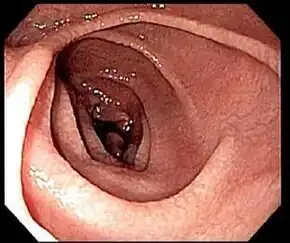

Most people with coeliac disease have a small intestine that appears to be normal on endoscopy before the biopsies are examined. However, five findings have been associated with a high specificity for coeliac disease: scalloping of the small bowel folds (pictured), paucity in the folds, a mosaic pattern to the mucosa (described as a "cracked-mud" appearance), prominence of the submucosa blood vessels, and a nodular pattern to the mucosa.[96]